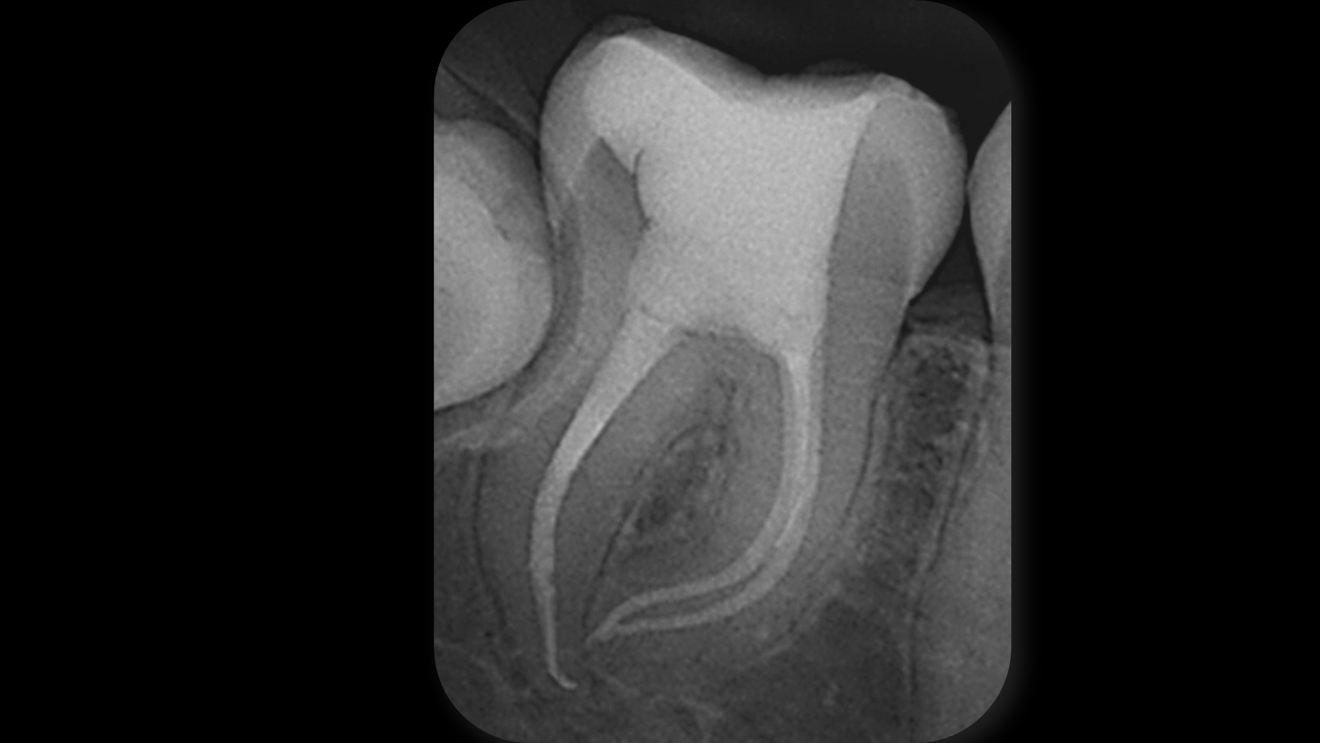

Fig. 4: Post-op radiograph of the mandibular right second molar showing dense obturation of all three curved canals and of a lateral canal in the distal root, indicating complete sealing of the canal system.

For obturation, a modified warm vertical compaction technique was applied at 150 °C using a customised gutta-percha cone. For the final seal and in support of the healing process, ROEKO GuttaFlow bioseal (COLTENE) was chosen. The angulated postoperative radiograph revealed dense filling of all canals and of an additional lateral canal in the distal root, confirming that the modified warm compaction technique and GuttaFlow bioseal had effectively sealed the entire canal system (Figs. 4 & 5).